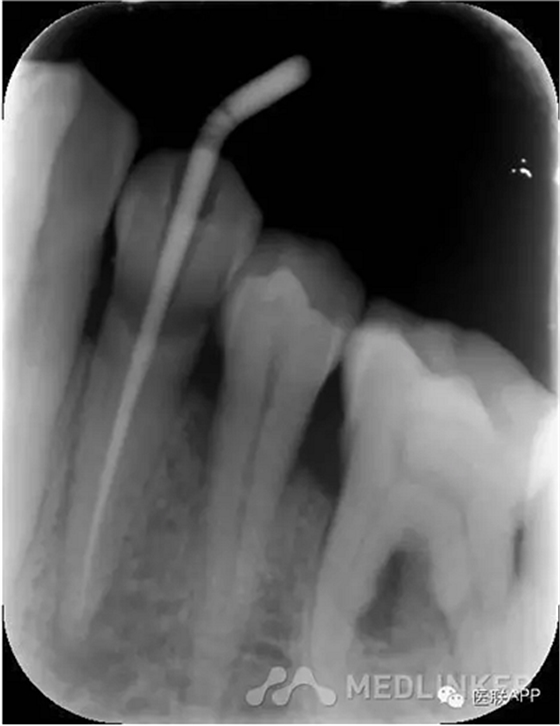

初診:頰側(cè)去腐,合面常規(guī)開髓揭頂,拔髓,電測根長WL=22mm,EDTA下手擴+機擴+protaper根備至F2,CR反復沖洗,干燥,Vitapex根充,ZOE暫封,約日復診。